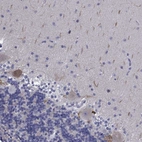

Immunohistochemical staining of human cerebellum shows cytoplasmic positivity in Purkinje cells.